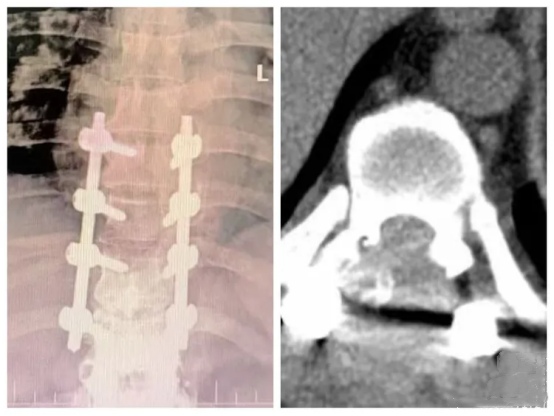

术前影像资料

术中影像资料